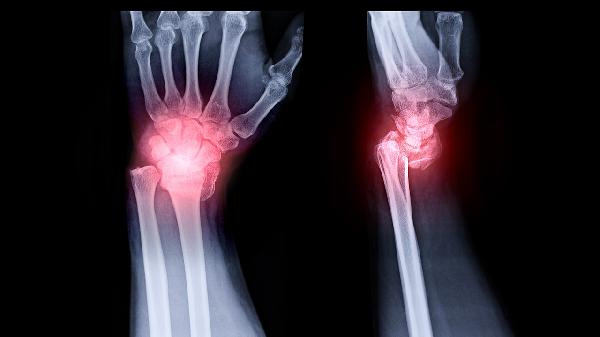

掌骨头骨折可以分为哪些类型

掌骨头骨折可分为关节内骨折、关节外骨折、粉碎性骨折、撕脱性骨折和压缩性骨折等类型。